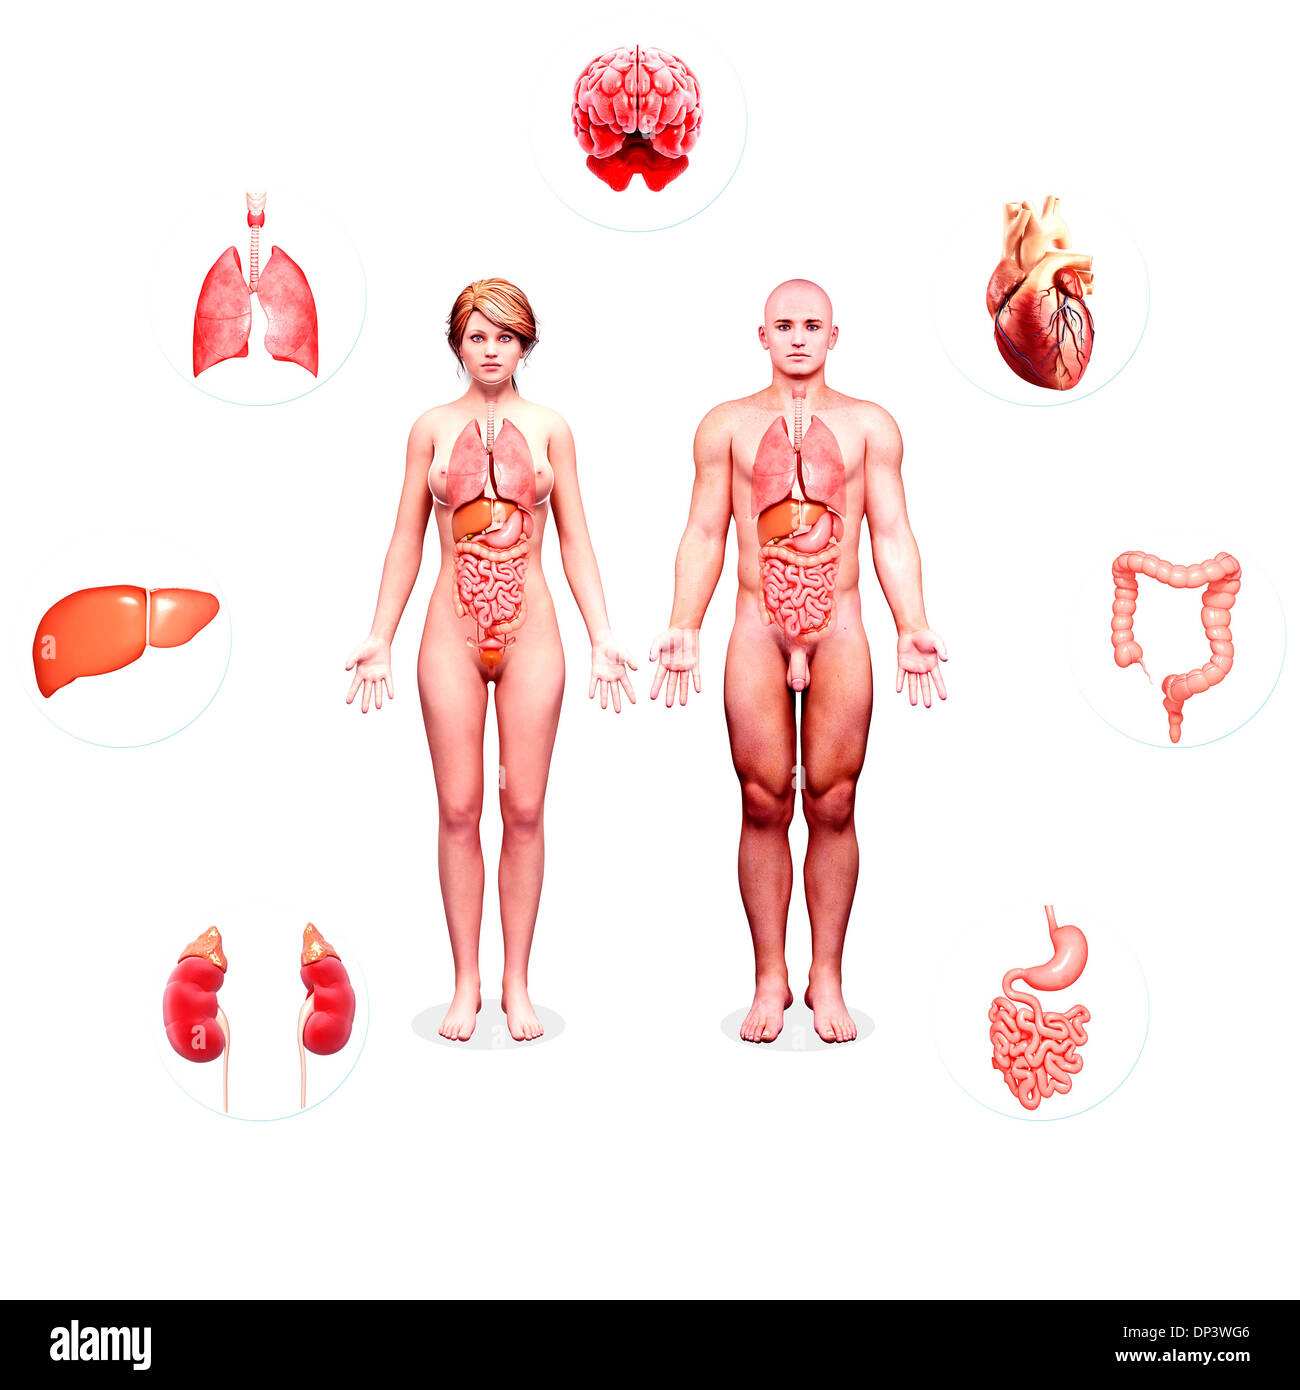

Human Anatomy, artwork Banque D'Imageshttps://www.alamyimages.fr/image-license-details/?v=1https://www.alamyimages.fr/human-anatomy-artwork-image65239446.html

Human Anatomy, artwork Banque D'Imageshttps://www.alamyimages.fr/image-license-details/?v=1https://www.alamyimages.fr/human-anatomy-artwork-image65239446.htmlRFDP3WG6–Human Anatomy, artwork